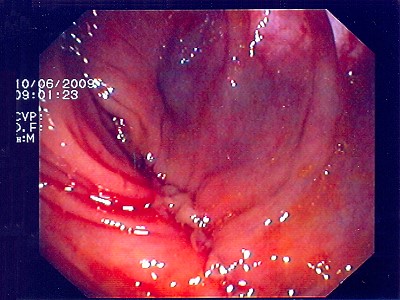

Polypabtragungsstelle